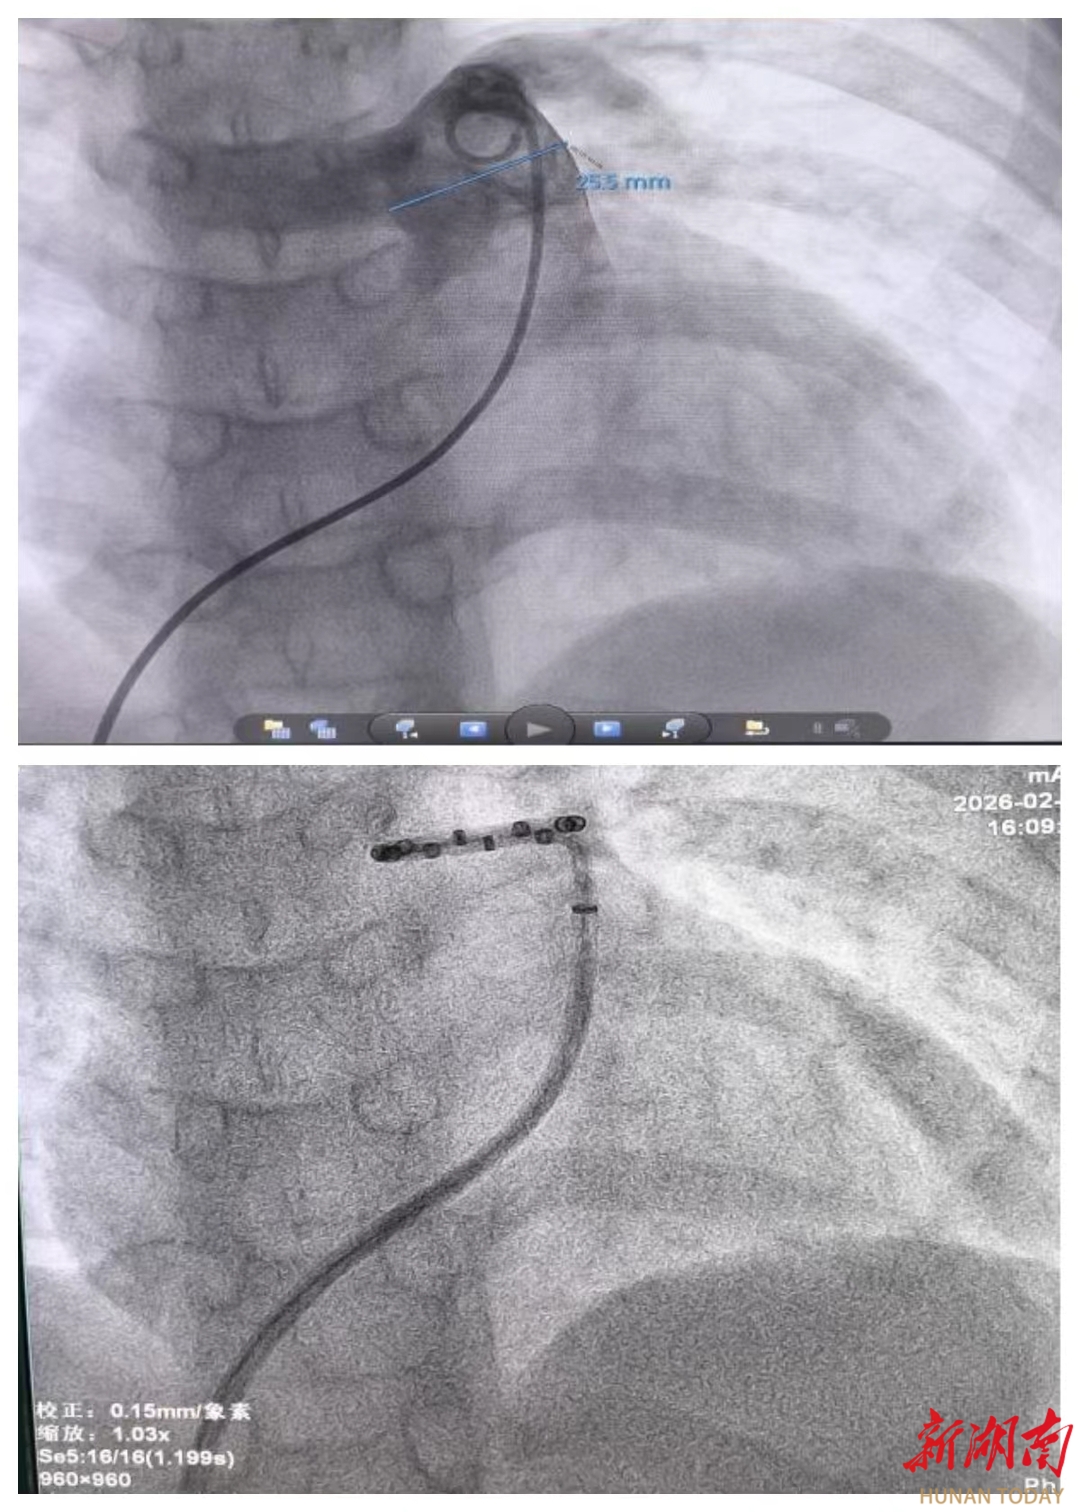

图为术中小涵肺动脉造影及消融导管定位影像

手术由心脏中心二病区肖云彬教授、杨舟教授主刀,在麻醉与监护保障下完成精准消融操作。术后即刻评估显示,小涵平均肺动脉压较术前下降26%,肺血管阻力下降17%。小涵术中及术后生命体征平稳,目前恢复良好,顺利出院。